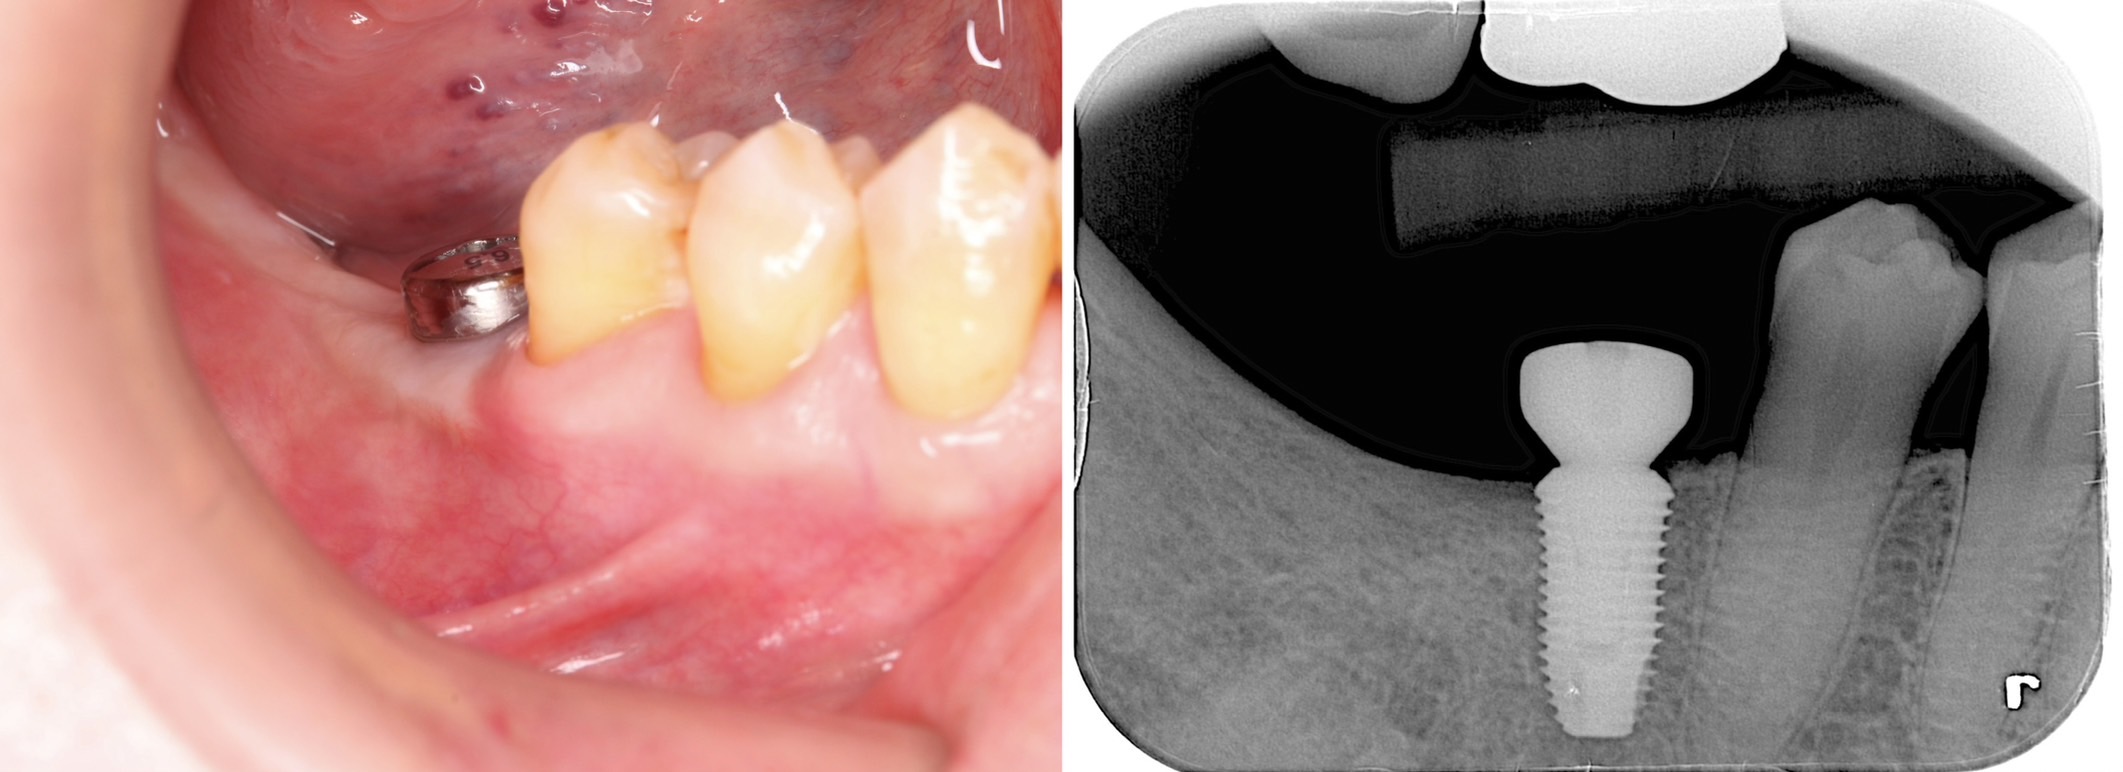

固定式假牙種類5:植牙

利用人工牙根和牙冠來取代缺牙的方法,具有以下3大優點:

1. 穩固且咬合功能強。

2. 可以單顆進行,無需破壞周圍正常牙齒。

3. 外表相當接近真牙,看起來美觀又健康。